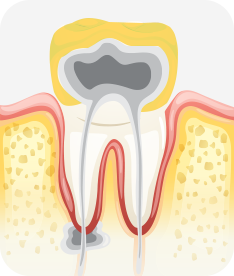

치수염 충치

밤에 잠을 이루지 못할 정도로 아프거나 찬 것과 뜨거운 것에 통증이 있을 수 있으며, 도중에 나은 것처럼 증상이 없어지는 경우도 있음. 치아의 경조직 뿐 아니라 치수까지 염증이 생긴 상태.

치료방법 신경치료, 크라운 등 보철치료

치아신경 염증

충치가 심해져 치아 뿌리까지 신경 염증이 발생함

신경소독

충치를 제거하고, 치아 뿌리 끝까지 신경관 내부의 염증 물질들을 제거하고 소독함

신경치료 완료

소독된 신경관을 생체친화적인 재료로 충전한 후 보철치료를 함